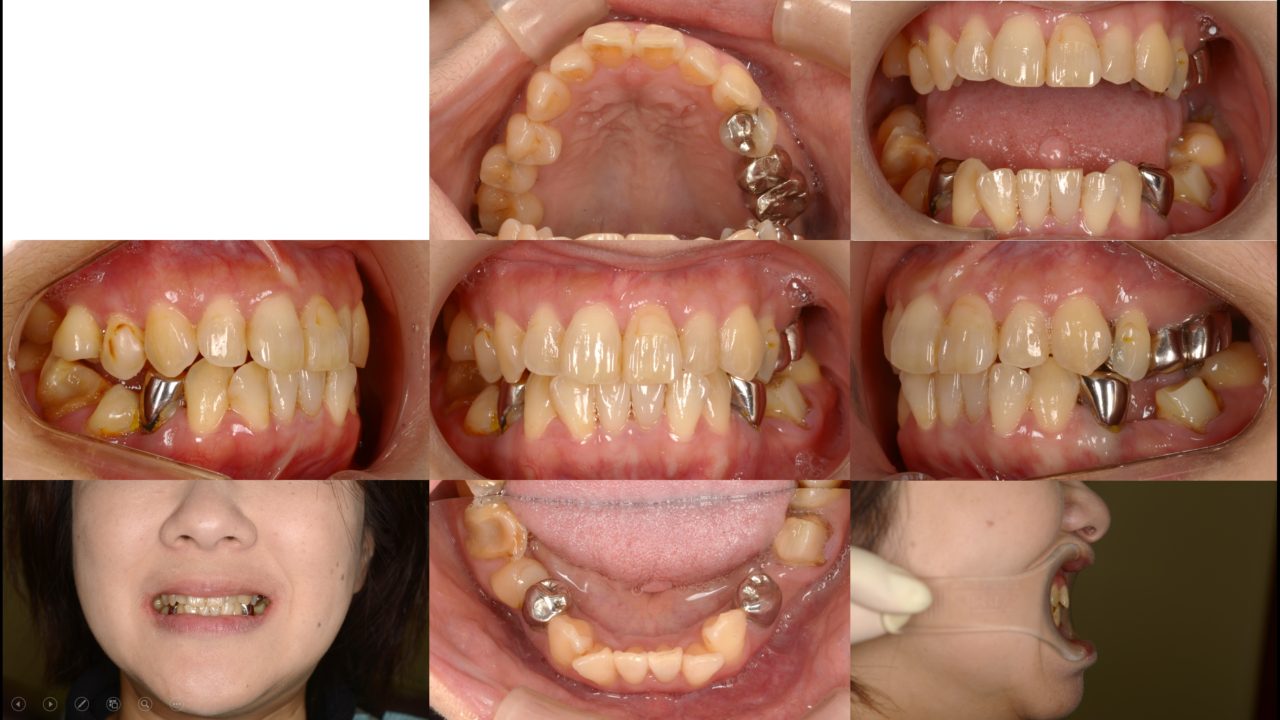

Before

| 主訴 | 奥歯で噛みにくい 奥歯の冠がよく外れる |

| 診断 | 両側アングルクラスⅢ叢生 |

| 備考 | 以前から当院に通院されている方で定期的に奥歯にトラブルを起こしていました。 下顎奥歯が左右ともに傾斜しており、いわゆる「噛み合わせが悪い」状態でした。 20年後までの歯のトラブルを考えて、噛み合わせと昔に治療した冠を全てコーディネートする フルマウスリコンストラクションをすることになりました。 歯の欠損があったので、2本はインプラントをしました。 矯正治療終了後、セラミックによる補綴治療を行い、噛み合わせのしっかりした状態を作りました。 しっかりメインテナンスをできるだけ再治療のない状態を目指します。 |

初診 2018.2.22